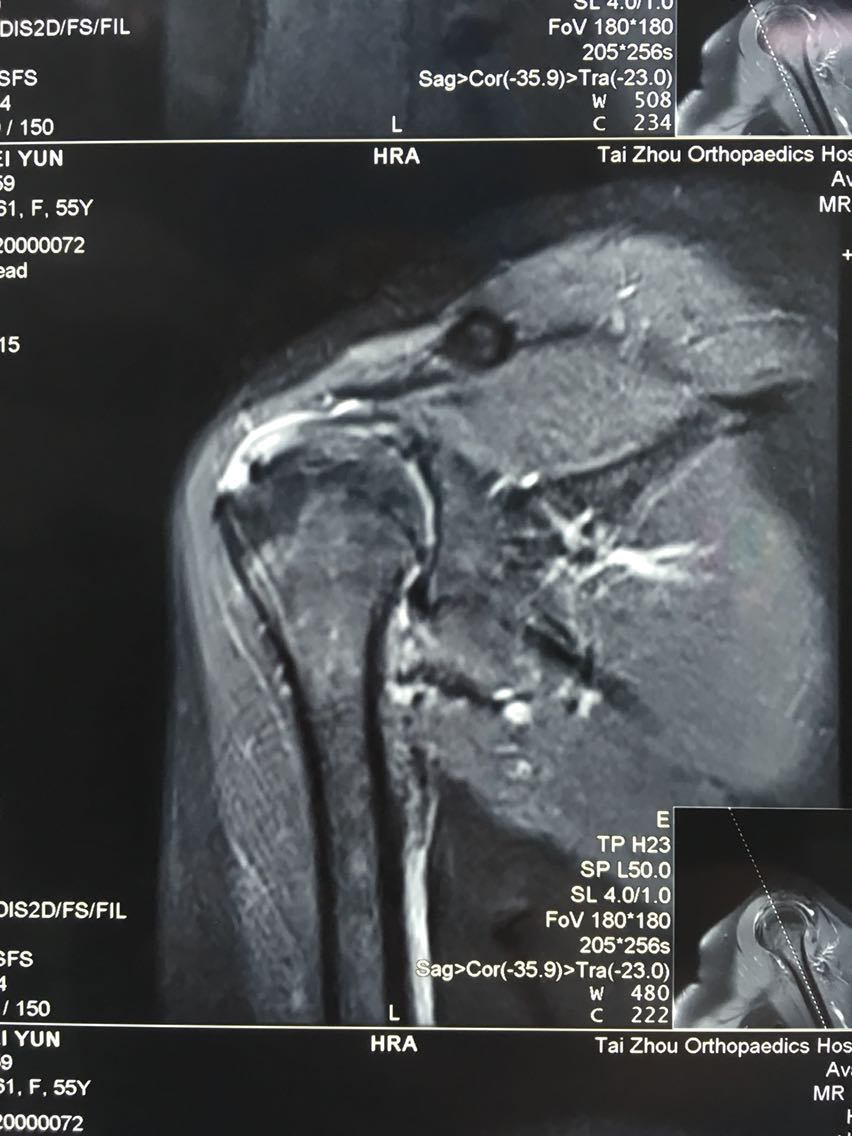

主诉:右肩关节疼痛、功能障碍6个月 现病史:患者于6个月前出现肩关节疼痛,以夜间明显,在当地医院诊断为肩周炎,给予指导关节功能锻炼,疼痛症状和功能障碍加重,效果不佳,来院就诊,核磁共振检查后,诊断为:肩袖撕裂 肩峰撞击症。收入院行关节镜下清理 肩峰成形 肩袖撕裂修补手术。

诊断:右肩袖撕裂 肩峰撞击症 冻结肩 治疗:关节镜下清理 肩峰撞击成形 肩袖撕裂修补手术。